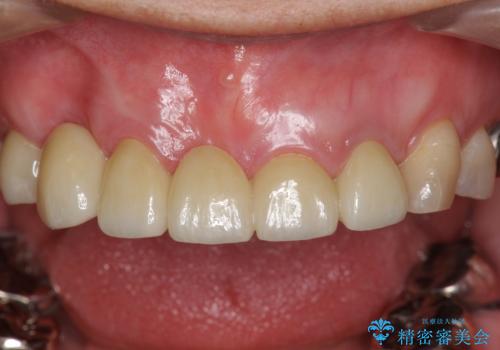

過度な咬合力 歯ぎしりで抜けた歯の欠損補綴

過度な力がかかり周囲の骨に高度な吸収が見られた犬歯は抜歯し、機能・審美性の回復をより咬合力に対して抵抗力のあるブリッジ補綴にて対応します。

- 56円(仮歯・フルジルコニアクラウン×7)費用は治療当時の料金となります

ブリッジによる欠損補綴を行ったのち、ナイトガードを夜間装着していただき歯を守ります。